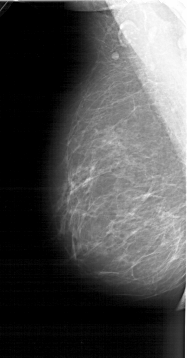

A_1403_1.LEFT_MLO

LEFT_MLO LINES 6436 PIXELS_PER_LINE 3361 BITS_PER_PIXEL 12 RESOLUTION 43.5 NON_OVERLAY